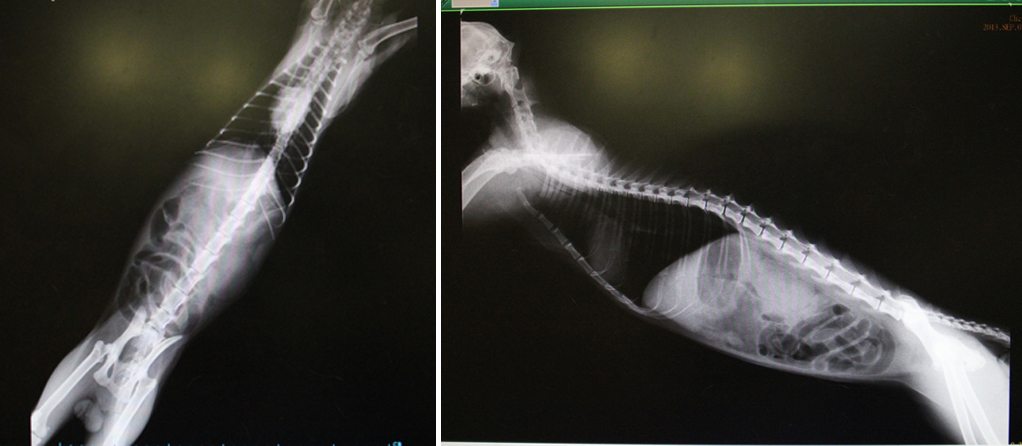

9/7:貧血、黃疸、檢驗無愛滋白血、X光片顯示腎臟很大,腸道部分有模糊的狀況,且觸摸腹部仍十分疼痛,研判腹膜炎的可能性極高.....